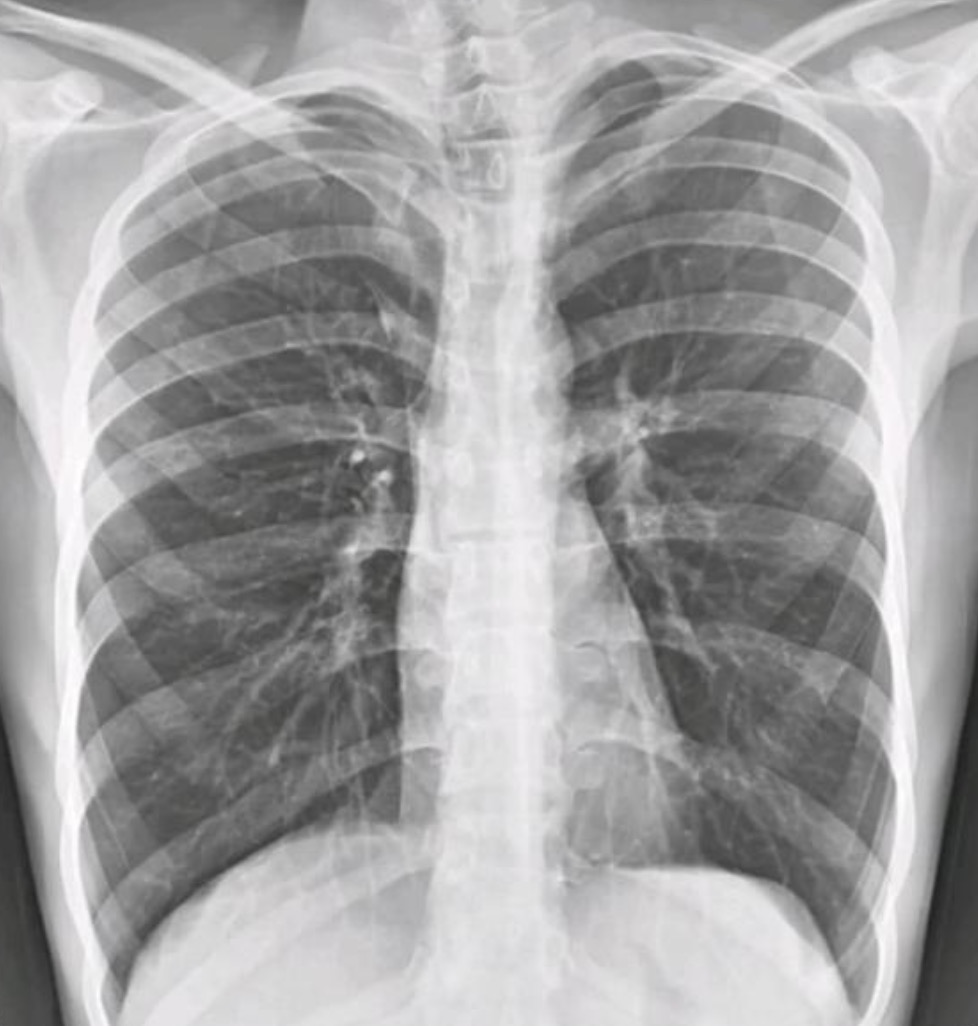

Ici, aucun de ces éléments n'est présent 👉 Le cliché montre au contraire une hyperclarté diffuse des deux champs pulmonaires avec des coupoles basses et des côtes horizontales, en parfait contraste avec l'aspect d'une pneumonie.

RP originale 👇

RP annotée 👇

Réponse B: Vrai. La radiographie de Mr M. présente les 4 signes cardinaux de distension thoracique liés à l'emphysème :

Ces signes traduisent un emphysème, complication fréquente de la BPCO. Attention ! la radio seule ne confirme pas le diagnostic — elle oriente seulement.

Chez ce patient fumeur de 67 ans hospitalisé pour probable exacerbation (il y a un mois) le diagnostic de BPCO doit être au premier plan.

Une radiographie thoracique normale se caractérise par des coupoles diaphragmatiques arquées et bien visibles, des côtes à orientation oblique descendante, un parenchyme pulmonaire de densité homogène avec une vascularisation visible jusqu'aux 2/3 externes, et un rapport cardiothoracique < 0,5. Ici, les 4 signes de distension sont présents et constituent une anomalie radiologique significative.